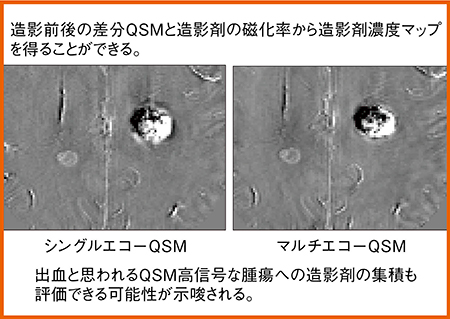

なお,QSMはマルチエコーで撮像することが多いが,日立の最新3T MRI「TRILLIUM OVAL Cattleya」にはシングルエコーQSMも搭載された。そこで,シングルエコーとマルチエコーのQSMを比較検討した。脳転移症例の造影前後の画像では,シングルエコーとマルチエコーで同等の画像が得られた。また,造影前後のQSMを差分し,造影剤濃度マップを作成すると,出血と思われる高信号が,シングルエコー,マルチエコーともに外側優位に描出された(図4)。QSM撮像においてはエコー数の影響はなく,造影剤集積も評価できる可能性がある。

図4 QSMによる造影剤濃度マップ(脳転移症例)